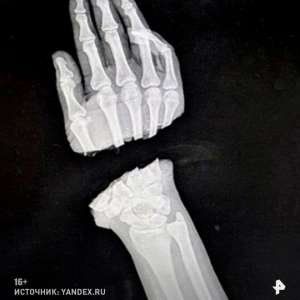

Можно ли восстановить руку, если она полностью отделена от тела? Посмотрите на это фото.

Специалисты из Санкт-Петербургского центра травматологии и ортопедии имени Вредена совершили невероятное. Сначала они совместили и зафиксировали костные фрагменты с помощью специальных металлических спиц.

Затем, используя микроскоп, они аккуратно соединили вены, артерии, сухожилия и нервы. Операция длилась целых семь часов!

Хотя последствия неосторожного обращения с деревообрабатывающим оборудованием, конечно, будут заметны, 28-летняя девушка сможет жить полноценной жизнью, имея обе руки!